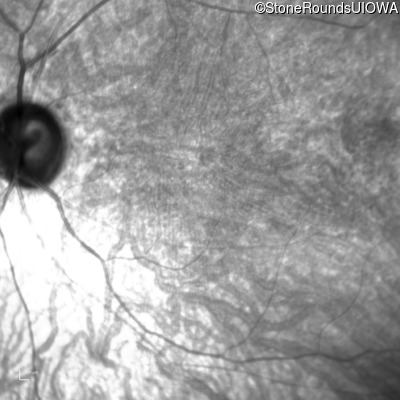

Infrared Fundus Photograph - Left - 20/200 +2

Exemplar